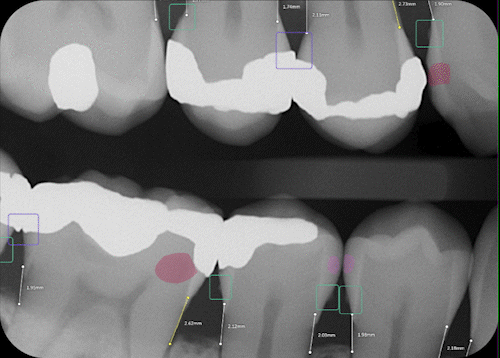

The dental patient journey has always begun in the dimly lit fog of a grayscale radiograph. Until now. When practices turn on the power of AI, x-rays burst with brilliance, offering a technicolor roadmap to dental health.

- Caries

- Periapical radiolucency

- Calculus

- Notable Margin

- Bone levels

- Impaction

- Restorations (Fillings, Crowns, Root Canals, Bridges, Implants)

- Tooth part mapping

- Tooth numbering

- Annotation & detectors

- AI Image Enhancement

- Measurement tool

Viewed under the bright lights of AI, x-rays show up with more clarity and focus, offering dentists a stronger diagnostic foundation for their treatment recommendations and giving patients real confidence that the treatment is necessary.

Color-coded and labelled overlays and take-home reports help patients clearly see the conditions affecting their dental health, facilitating informed consent to treatment.

Data-driven radiologic insights improve the scientific credibility of diagnoses and enable more trustworthy, precise and individualized treatment planning and case presentation.